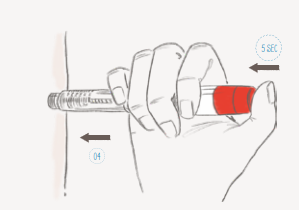

Deze laatste stap is bij beide schema’s gelijk. Als bij echoschopisch onderzoek blijkt dat de eiblaasjes voldoende groot zijn en de hormoonspiegel van het Oestradiol in het bloed goed gestegen is, wordt de stimulatie afgerond door de toediening van de Ovitrelle ® injectie. Deze injectie zet de laatste rijpingsfasen van de eicel(len) in gang. Deze zeer belangrijke, onmisbare injectie sluit de stimlatiefase af en moet altijd ’s avonds op een afgesproken tijdstip worden toegediend. Ook deze injectie spuit de patiënt zelf.